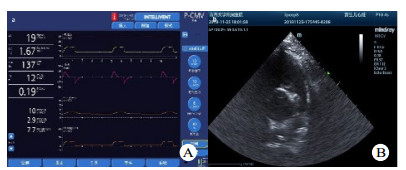

| A:为瑞士HAMILTON·G5呼吸机;B:肺动脉漂浮导管位置 图 1 本实验所用呼吸机及心脏超声机 Fig 1 Ventilator and echocardiography used in this experiment |